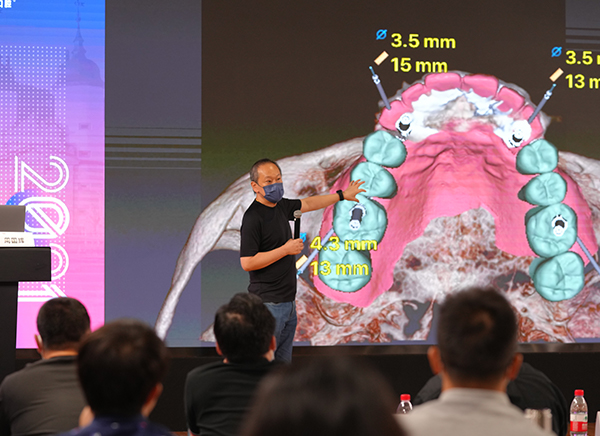

坚守学术至上 ,推行教研合一

建院至今,

海德堡联合口腔共举办了

数十场国内外学术会、交流会、分享会、培训会

十余国、超百位学者参与其中

这个数字还在持续增加……

重视学术研究,人才培养,

为提高口腔医疗质量

更为患者提供优质严谨的诊疗服务